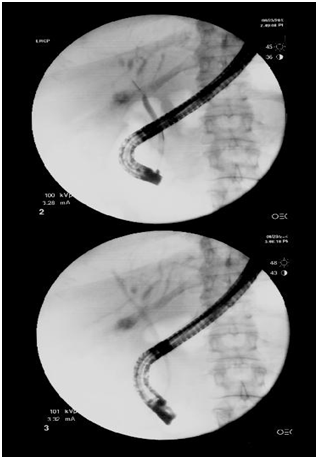

Emergent ERCP (Figure 3) was done and findings were consistent with the Mirizzi syndrome type I and also showed a biliary stricture in the distal right intrahepatic system extending to the common hepatic duct. The right intrahepatic system was stented at the level of the right intrahepatic and there was dilatation noted on the left side. The patient underwent a follow up cholecystectomy during which intraoperative findings showed an edematous & non-gangrenous GB. The cholecystectomy specimens and the biopsy of the CBD strictures were sent to pathology for histo-pathological correlation.

Figure 3 ERCP image.